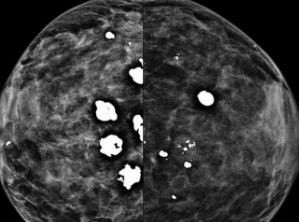

Dê o BI-RADS

2: benigno, patognomônico de fibradenoma

“em pipoca”